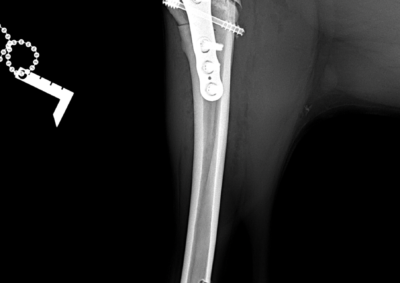

注意 ボタンをクリックした先に、治療中および手術中の画像が説明で使用されている場合がございます。 そのような画像に弱い方は閲覧なさらないようお願いいたします。 整形外科 若齢犬の橈骨固定術 #271 整形外科 前十字靭帯断裂(中型犬)に対するCBLO #255 整形外科 超小型犬に対する上腕骨遠位Y字骨折 整形外科 大型犬の前十字靭帯疾患(慢性経過)に対するCBLO #254 整形外科 橈骨固定術 #270 整形外科 膝蓋骨内方脱臼に対する人工滑車置換術 PGR #23 整形外科 犬の前十字靭帯(疾患)部分断裂に対するCBLO #253 整形外科 犬の前十字靭帯断裂に対するCBLO #252 整形外科 膝蓋骨内方脱臼+前十字靭帯断裂に対するPGR#22・LSS 整形外科 大腿骨骨折 整形外科 橈骨固定術 #269 整形外科 上腕骨外顆骨折の癒合不全 123456> 症例カテゴリー 放射線治療整形外科軟部組織外科脳神経外科内科腫瘍外科救急・集中治療リハビリテーション科腫瘍内科内視鏡科脳神経科呼吸器外科中医・漢方猫の腎移植循環器科